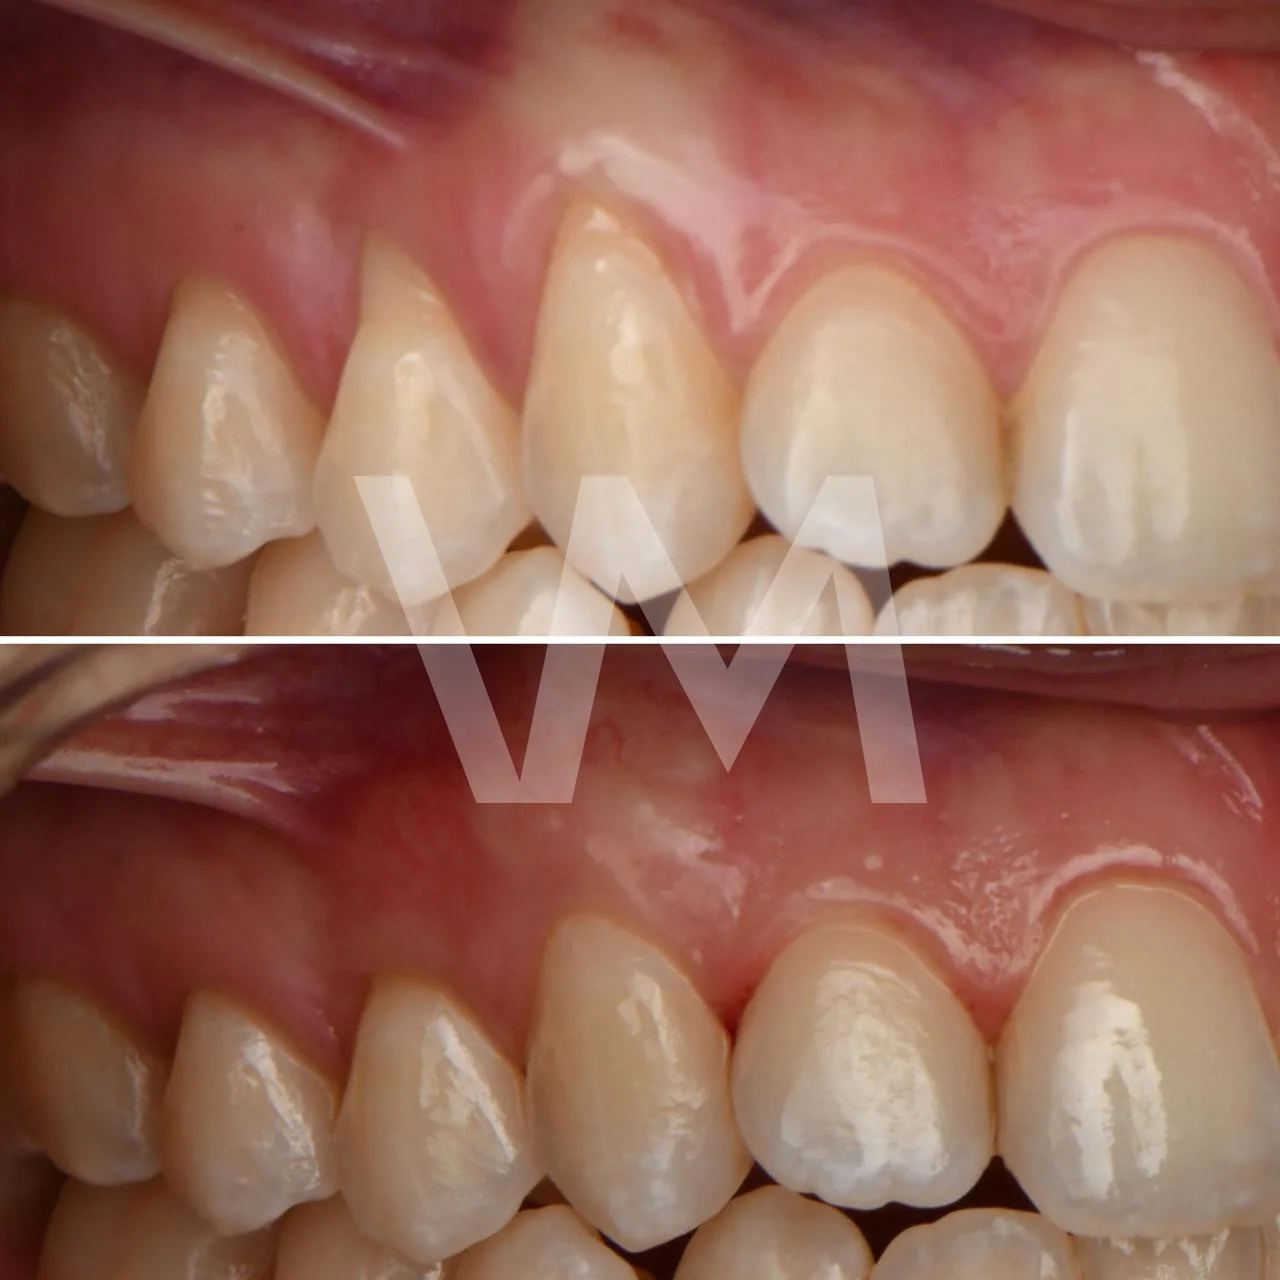

Injertos de encía

Cirugías de Injertos de Encía del Paladar e Injertos Sintéticos para el Tratamiento de Recesiones Gingivales

Las recesiones gingivales son un problema común en el que las encías retroceden, dejando expuesta la raíz del diente y aumentando el riesgo de sensibilidad dental, deterioro del hueso y pérdida de dientes. Para corregir estas recesiones y restaurar la salud gingival, se pueden realizar cirugías de injertos de encía del paladar e injertos sintéticos.

Casos clínicos realizados por la Dra. Paulina